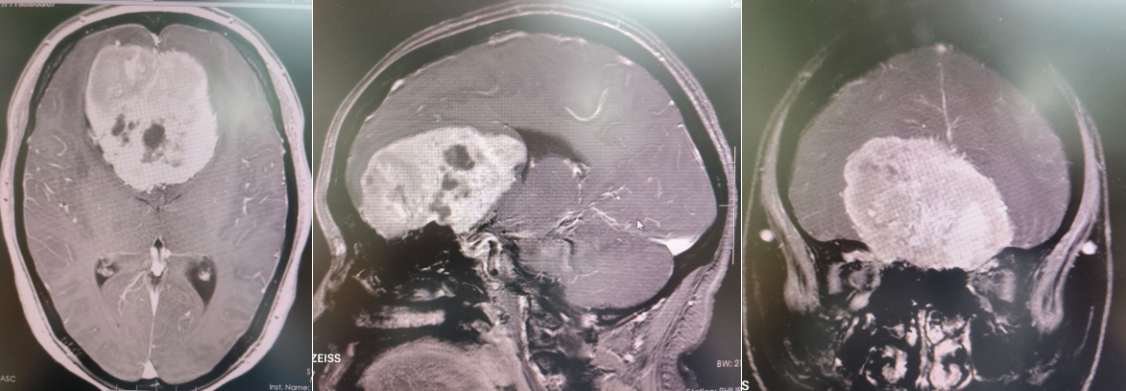

该患者突发剧烈头痛,持续一周未见缓解,经磁共振检查发现前颅窝底存在巨大占位性病变,初步诊断为嗅沟脑膜瘤。突如其来的重病让患者及家属陷入焦虑,而患者特殊的生理时期(产褥期)叠加高血压、先心病、肺动脉高压、贫血、低蛋白血症、电解质紊乱等多重基础疾病,手术风险极高。

术前

面对复杂病情,蒲军主任团队迅速启动多学科协作机制,联合麻醉手术科、ICU、心脏血管外科、血液内科等科室专家开展会诊,全面评估患者身体状况,精准制定围手术期安全保障方案。术中,团队发现肿瘤血供丰富,手术操作难度极大。蒲军主任带领团队精准切断肿瘤基底、阻断血供,分块细致切除,最终成功实现肿瘤全切,有效解除患者病痛。术后,患者头痛明显缓解,未出现神经系统损伤,恢复良好。